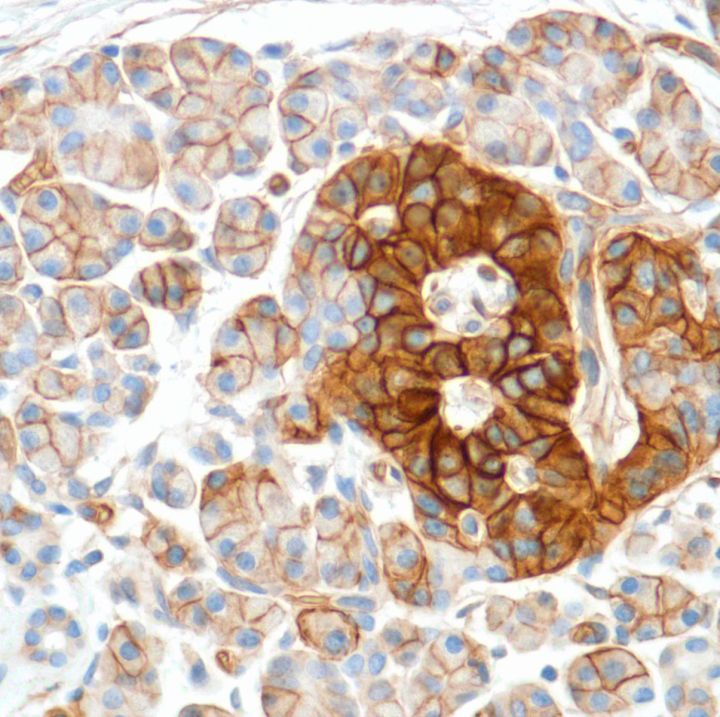

Human equilibrative nucleoside transporter 1 (hENT1) is a member of the equilibrative nucleoside transporter family. It is a transmembrane glycoprotein that localizes to the plasma and mitochondrial membranes and mediates the cellular uptake of nucleosides from the surrounding medium. The protein is sensitive to inhibition by nitrobenzylthioinosine (NBMPR). It is considered as a drug carrier. Nucleoside transporters such as hENT1 are required for nucleotide synthesis in cells that lack de novo nucleoside synthesis pathways, and are also necessary for the uptake of cytotoxic nucleosides used for cancer and viral chemotherapies.